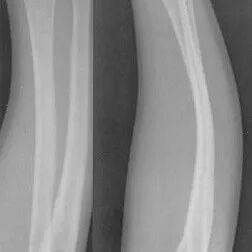

The third type is called a bowing fracture or a plastic fracture. It happens when the bone becomes bent but does not break, as seen in the image below.